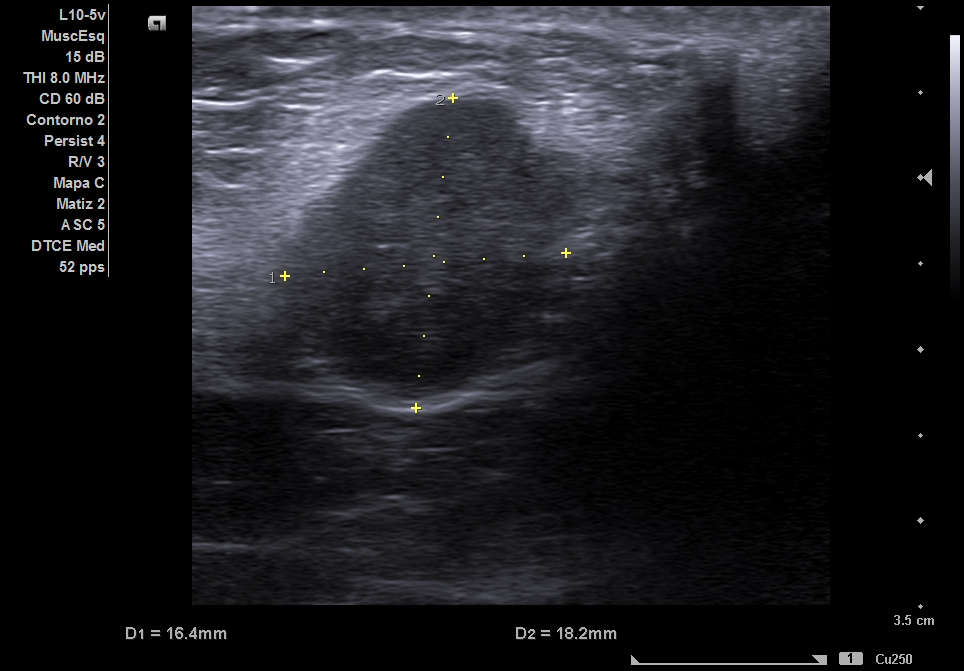

Ecografía clínica partes blandas y abdominal en Centro de Salud: dos nódulos subcutáneos hipoecogénicos, heterogéneos, lobulados y de bordes irregulares (16 x 18 mm), no vascularizados. Abdomen: sin signos patológicos relevantes ni Ascitis ni líquido en Douglas no adenopatías retroperitoneales. Completamos estudio de nódulos sospechosos de malignidad con tomografía abdominal y ecografía de partes blandas reglada.

Ecografía reglada de partes blandas: Nódulos subcutáneos e intrabdominales sospechosos de malignidad. La tomografía abdominal describe múltiples implantes sólidos peritoneales y en pared abdominal, compatibles con metástasis.